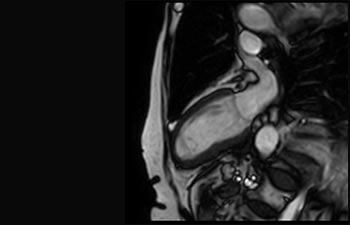

D.ssa Silvia Schiffer, Direttore e Senior Radiologo presso l'istituto Radiologie Schiffer in Germania, racconta le sue esperienze con il sistema RM Ingenia Prodiva 1.5T.

I primi utilizzatori di Ingenia Prodiva 1.5T raccontano le loro esperienze nell'uso del sistema e spiegano di come questo influisce sulle attività del centro diagnostico.